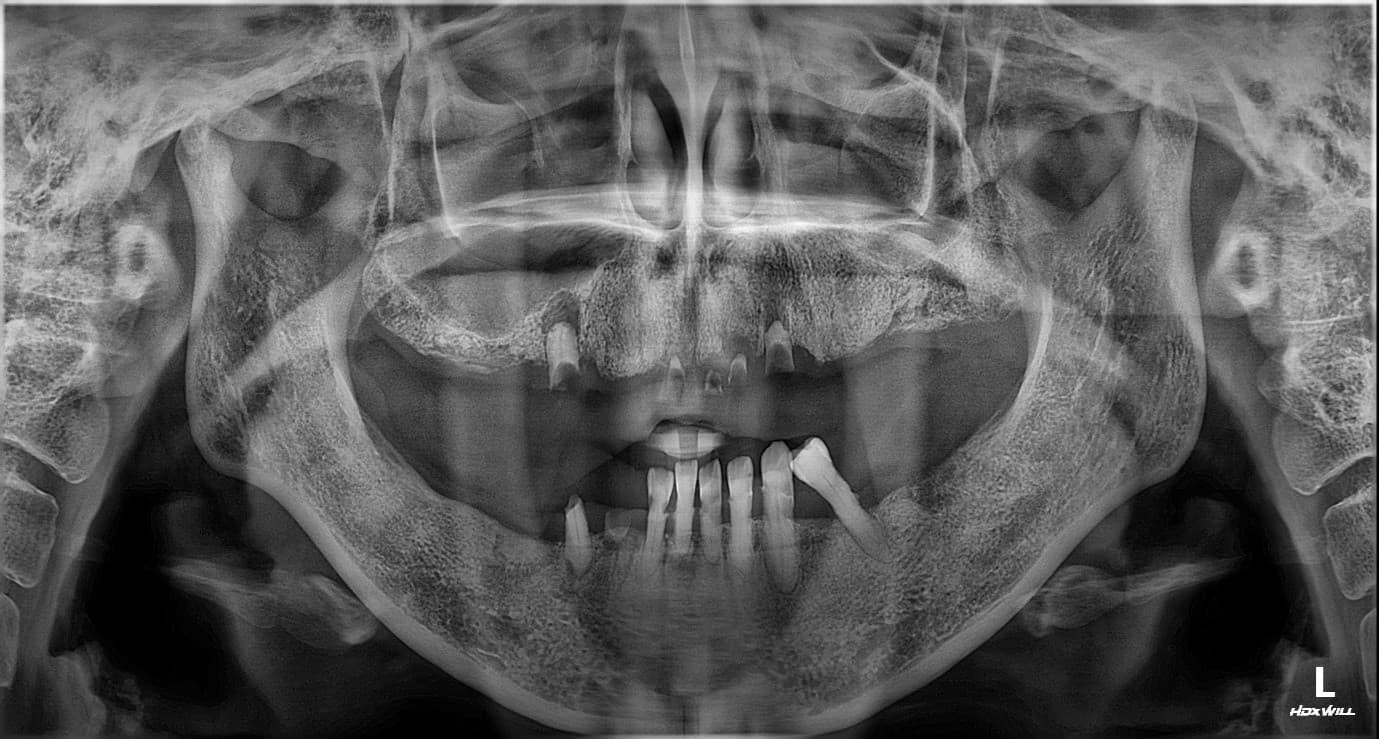

김○님님 치료 사례

구강 사진

치료 전

X-ray